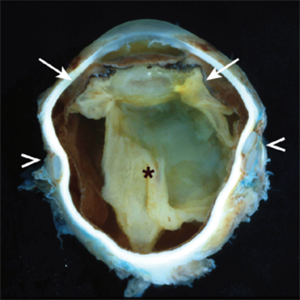

Nongranulomatous uveitis is a group of diseases often related to systemic autoimmune diseases such as arthritis. This image shows a thickened uveal track (arrows) and a complete, long-standing retinal detachment (*). The lens is cataractous and the iris, ciliary body, and parts of the retina are attached to it. A scleral buckle is present (arrowheads).